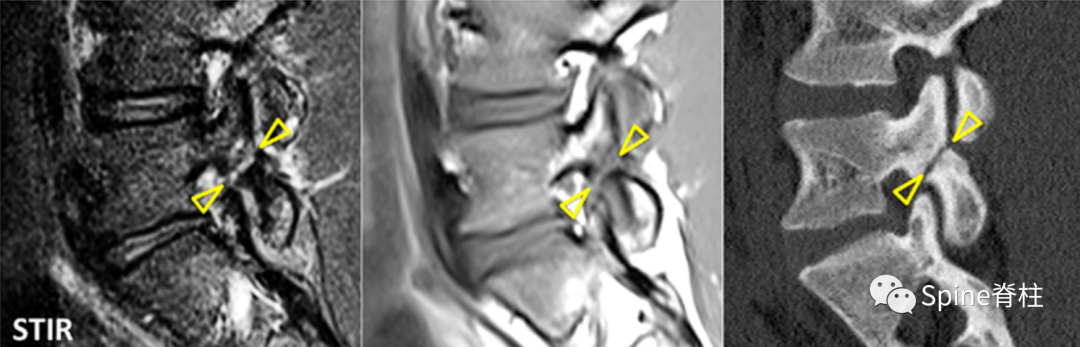

图:孤立的峡部水肿信号,提示L5右侧峡部裂(1级)

16岁的足球运动员诉右腰部疼痛。A:右侧T1加权像可见腰5峡部和椎弓根呈低信号(箭头);B:右侧T2加权像可见腰5峡部、椎弓根和关节突呈高信号(箭头)。

图:T2水肿信号且峡部皮质不连续断裂

提示L3左侧峡部裂(2级)

17岁的篮球运动员诉腰痛。A:T1像,左侧腰3峡部呈不连续的低信号(箭头);B:T2像,左侧腰3椎弓根和峡部呈高信号(箭头)

图:峡部完全断裂,断端存在明显间隙,且T2像明显水肿信号,提示L5左侧峡部裂(3级)

16岁的足球运动员,诉腰痛,以左侧为重。A:T1像可见腰5左侧峡部完全断裂(箭头);B:T2像,腰5左侧峡部、椎弓根和关节突水肿信号(箭头)

图:峡部完全断裂,但无T2水肿信号

提示为左侧L5峡部裂(4级)

13岁运动员,左侧腰骶部疼痛。A:T1像,左侧腰5峡部完全断裂(箭头);B:T2像,左侧腰5峡部清晰可见,骨质无信号改变,峡部缺损处可见轻微的高信号,提示可能为肉芽组织或积液